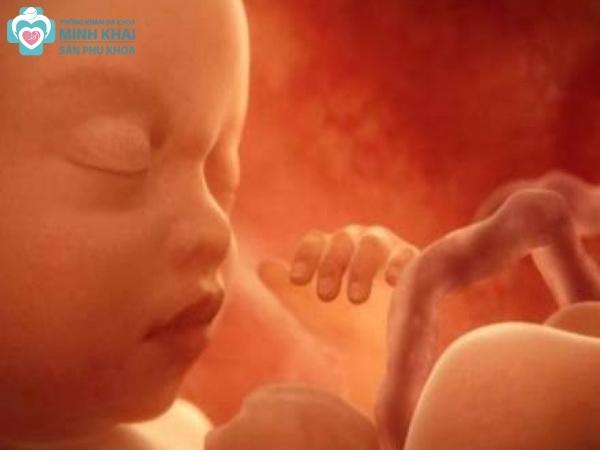

Siêu âm 5D TPHCM hay siêu âm thai 5D là kỹ thuật chẩn đoán hình ảnh hiện đại, sử dụng sóng siêu âm để tái tạo hình ảnh động của thai nhi bên trong tử cung người mẹ. Với phương pháp siêu âm 5D , mẹ bầu có thể lưu trữ, quan sát những hình thái, chuyển động và thậm chí là biểu cảm dù nhỏ nhất của con với hình ảnh rõ nét, chân thực. Không chỉ vậy, siêu âm màu 5D giúp bác sĩ phát hiện sớm các dị tật của em bé ngay từ giai đoạn đầu tiên của thai kỳ.

Hình ảnh siêu âm 5D có độ phân giải cao và có thêm màu sắc sống động. Nó giống như thước phim ngắn thể hiện được trọn vẹn sự vận động, trạng thái cũng như biểu cảm của thai nhi trong bụng mẹ một cách chi tiết nhất.

Với siêu âm thai 5D, các hoạt động và cử chỉ của thai nhi sẽ được hiển thị một cách chi tiết ngay trong thời gian thực. Ba mẹ gần như sẽ được quan sát bé qua thước phim màu ngắn để nắm trọn từng khoảnh khắc của bé con. Ngoài ra, các mặt cắt hình ảnh không gian đa chiều này còn hỗ trợ bác sĩ chẩn đoán chính xác được các bất thường của thai nhi.